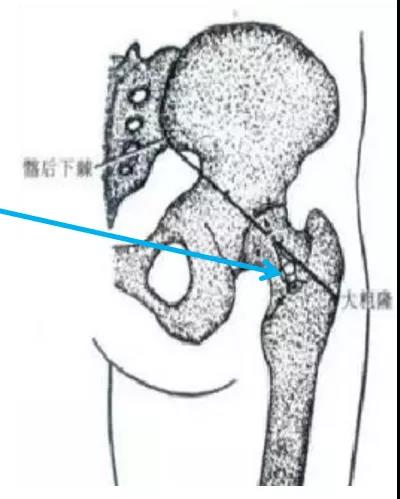

侧路进针法(大转子尖端进针法):患者侧卧位,患侧在上。在股骨大转子尖上方为穿刺点。常规消毒铺巾,用7号长穿刺针刺入,并徐徐沿股骨颈上缘骨面向上方髋臼进入,至髋臼关节囊外,后抽无血后,即可注射药物;在继续进针可进入关节腔。

后路进针法:患者俯卧位,或侧卧位,患侧在上。在大粗隆中点与髂后下棘连线的中、外1/3交界处为穿刺点。常规消毒铺巾,用7号长穿刺针垂直或稍向上刺入,至骨面后稍退针,此时针尖在关节腔内。